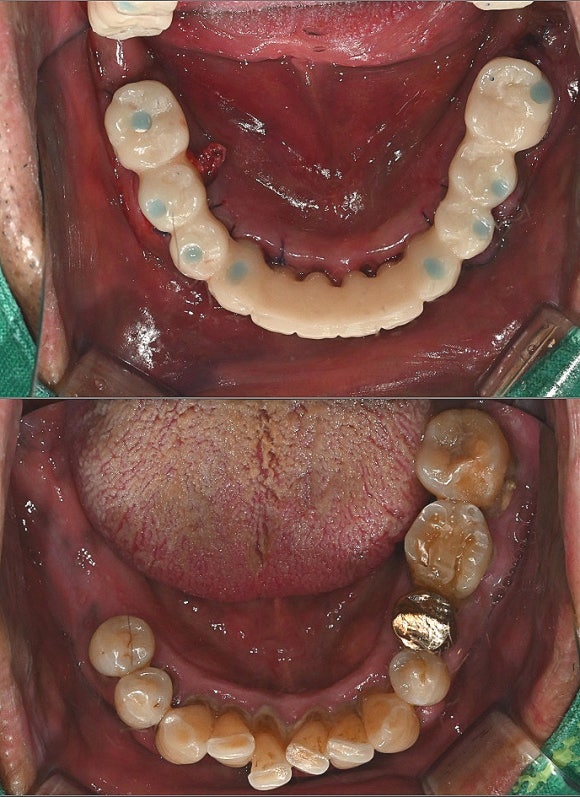

발치 12개임플란트 8개 식립

뼈 상태와 고정력이 안정적으로 나와

다음날 임시치아

바로 장착하기로 결정했습니다.

여기서 중요 포인트는,

잇몸을 누르지 않는 구조의

임시치아 라는 점입니다.

아직 실밥이

선명하게 보이는 시기지만

환자분은 바로

식사와 대화가 가능한 상태가 됩니다.

즉,

진짜 의미의 “원데이 보철” 이죠.